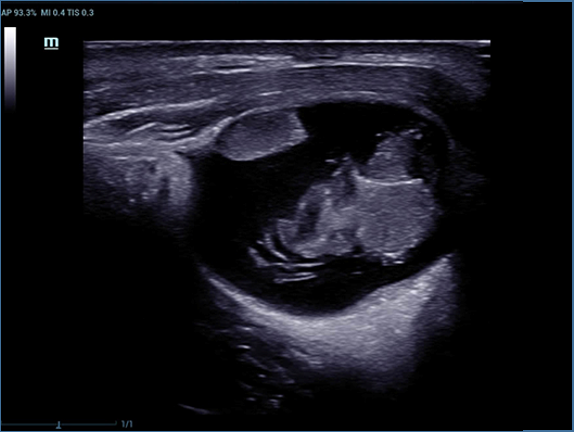

Mindray, ?irketin kuruldu?u gĂŒnden bu yana sĂŒrekli olarak tan?sal do?rulu?u iyile?tirmeye ?al??maktad?r. Devrim niteli?indeki ZONE Sonography? Teknolojisi ile desteklenen Resona 7ânin yeni ZST+ platformu, b?lge g?rĂŒntĂŒsĂŒ alma ve kanal veri i?leme ?zellikleri ile ultrason g?rĂŒntĂŒsĂŒ kalitesini daha ĂŒst bir dĂŒzeye ??kar?yor.

Resona 7, ĂŒstĂŒn dĂŒzeyde g?rĂŒntĂŒ kalitesine ek olarak, vaskĂŒler hemodinamik de?erlendirmesi i?in devrim niteli?indeki V Ak??? ile fetĂŒs CNS tan?lamas? i?in 3 boyutlu veri kĂŒmesinden dĂŒzlem g?rĂŒntĂŒsĂŒ alma konusunda en iyi birime sahip oldu?undan, klinik ara?t?rma yeterliklerini de art?rmaktad?r. En sezgisel, harekete dayal? ?oklu dokunmatik i?letim ile tĂŒm temel klinik ?zellikleri bir araya getiren Resona 7, ultrason yenili?i konusunda ger?ek anlamda yeni dalgalara ?ncĂŒlĂŒk ediyor.